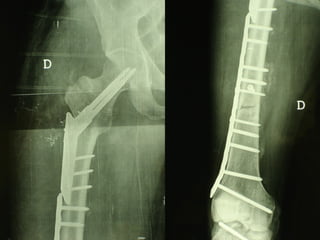

Dal Gennaio 2000 al Dicembre 2005 27 placche LISS di femore

INDICAZIONI COMUNI Fratture sovracondiloidee Fratture intercondiliodee Fratture diafisarie distali PARTICOLARI Fratture con grave osteoporosi Fratture periprotesiche

VANTAGGI CHIRURGIA MININVASIVA Mini Open Inserimento della placca sottocutaneo per scivolamento Viti percutanee Preservazione dei tessuti molli Ridotto danno vascolare Rapida ripresa funzionale

F, 68 y

LISS  NCB

NCB